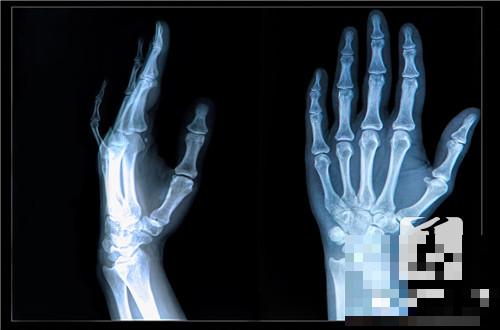

4、几处特殊部位

踝关节的胫腓联合螺钉,在下地负重前一定要取掉;脊柱骨折手术如果没有做融合,脊柱节段间会有反复微动。再结实的钢钉也经不起反复折弯,内植物容易出现疲劳性断裂。所以在骨折愈合后也要尽快取出。